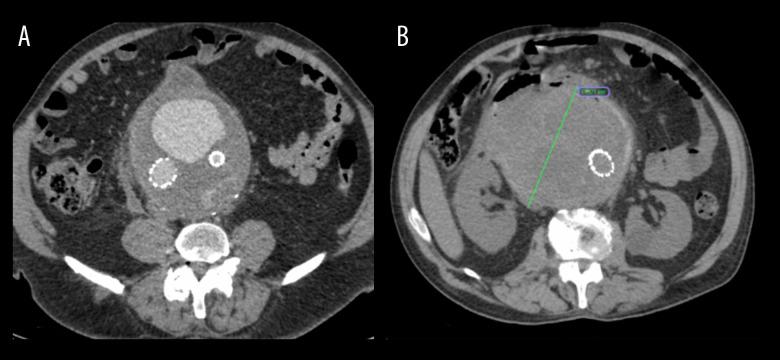

BACKGROUND Aorto-duodenal fistula (ADF) is a communication between the aorta and the duodenum and requires urgent aortic repair. However, it often leads to life-threatening complications. Thus, an early and appropriate diagnostic method is necessary to deliver adequate treatment. This report describes the case of a 68-year-old man with anaorto-duodenal fistula following emergency endovascular repair of a 14-cm abdominal aortic aneurysm (AAA) identified using oral contrast computed tomography (CT), and discusses the consequences of delayed treatment and ADF management. CASE REPORT We present a case of a 68-year-old White man with abdominal bloating, who upon further examination was diagnosed with an AAA, which was successfully treated by endovascular aneurysm repair (EVAR). However, 1 year later, an endoleak was discovered and, despite the physicians' efforts, the overall treatment was complicated due to the patient's continuous postponement of treatment over several years. The aneurysm continued to expand until it reached 14 cm. Despite the successful endovascular repair of the endoleak, a duodeno-aortic fistula (DAF) was diagnosed using CT with oral contrast. The patient was managed conservatively with aneurysmal sac drainage and antibiotic therapy, which decreased the size of the aneurysmal sac. Despite early diagnostic efforts and interventions, the patient's condition deteriorated due to further complications, ultimately resulting in death. CONCLUSIONS This case report demonstrates a potential useful diagnostic role of CT with oral contrast in detecting DAF, in situations when other methods fail to do so, and emphasizes the importance of prompt intervention to prevent life-threatening complications. However, further investigations to explore the underlying mechanism and its replicability are required.

背景 主动脉十二指肠瘘(ADF)是主动脉与十二指肠之间的连通,需要紧急进行主动脉修复。然而,它常常导致危及生命的并发症。因此,需要一种早期且合适的诊断方法来进行充分治疗。本报告描述了一例68岁男性患者,在使用口服对比剂计算机断层扫描(CT)确诊为14厘米腹主动脉瘤(AAA)并进行紧急血管内修复后发生主动脉十二指肠瘘的病例,并讨论了延迟治疗的后果及ADF的处理。病例报告 我们报告一例68岁白人男性患者,有腹部胀满症状,进一步检查诊断为AAA,通过血管内动脉瘤修复术(EVAR)成功治疗。然而,1年后发现内漏,尽管医生努力,但由于患者多年来持续推迟治疗,整体治疗变得复杂。动脉瘤持续扩大直至达到14厘米。尽管成功进行了内漏的血管内修复,但通过口服对比剂CT诊断出十二指肠主动脉瘘(DAF)。患者接受了动脉瘤囊引流和抗生素治疗的保守治疗,这减小了动脉瘤囊的大小。尽管进行了早期诊断和干预,但由于进一步的并发症,患者病情恶化,最终导致死亡。结论 本病例报告表明,在其他方法无法检测到DAF的情况下,口服对比剂CT在检测DAF方面具有潜在的有用诊断作用,并强调了及时干预以预防危及生命并发症的重要性。然而,需要进一步研究以探索其潜在机制及其可重复性。